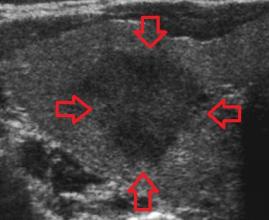

- Tiroid iltihabı (Hashimoto)

- Hashimato'da lazer tedavisi: İlaç dozlarının azaltılması veya kesilmesi ve kilo kontrolü !!!

- Hashimoto hastalığında destek tedavileri